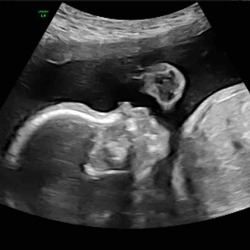

Ik had een knobbel tijdens mijn eerste zwangerschap. Echo gaf toen onvoldoende uitsluitsel dus kreeg een biopt. Gelukkig waren het toen twee types goedaardige tumoren, waarvan 1 gerelateerd aan melkklierweefsel en dus gerelateerd aan zwangerschap. Echter kan het ook zomaar wel iets niet oké zijn, dus goed om het snel te laten onderzoeken! Succes

Hi, ik had dit ook in mijn zwangerschap. Aan de zijkant van mijn borst. Daar zat echt een knobbeltje, ong zo groot als een knikker. Ik schrok mij wild, ook omdat mijn oma borstkanker heeft gehad. Ja en googlen moet je al helemaal niet doen. Ik ben door de huisarts verwezen voor een scan. Die zei ook, altijd laten checken. Uit de scan bleek dat dit een goedaardige zwelling was. Het was zoiets als dat je verkouden bent, dan kunnen de klieren ook opspelen, dit wordt dan een hard knobbeltje. Het hoefde niet weg en kan zelfs altijd zo blijven zitten. Mijn zoon is nu bijna 7 maanden en ik heb het knobbeltje nog steeds. Vind het wel gek. Maar ik was na de scan of echo , zo blij dat het niks ernstigs was. Daarom, goed dat je maandag heen gaat. En laat je doorverwijzen naar het ziekenhuis voor een echo. Dan weet je het maar zeker wat het is!